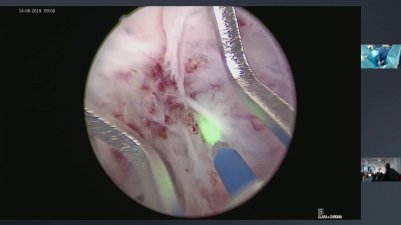

umpotolaryngologia

14:10 duration

0 likes